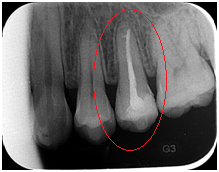

【根尖片】

◆磨牙龋齿

◆根管治疗完成后